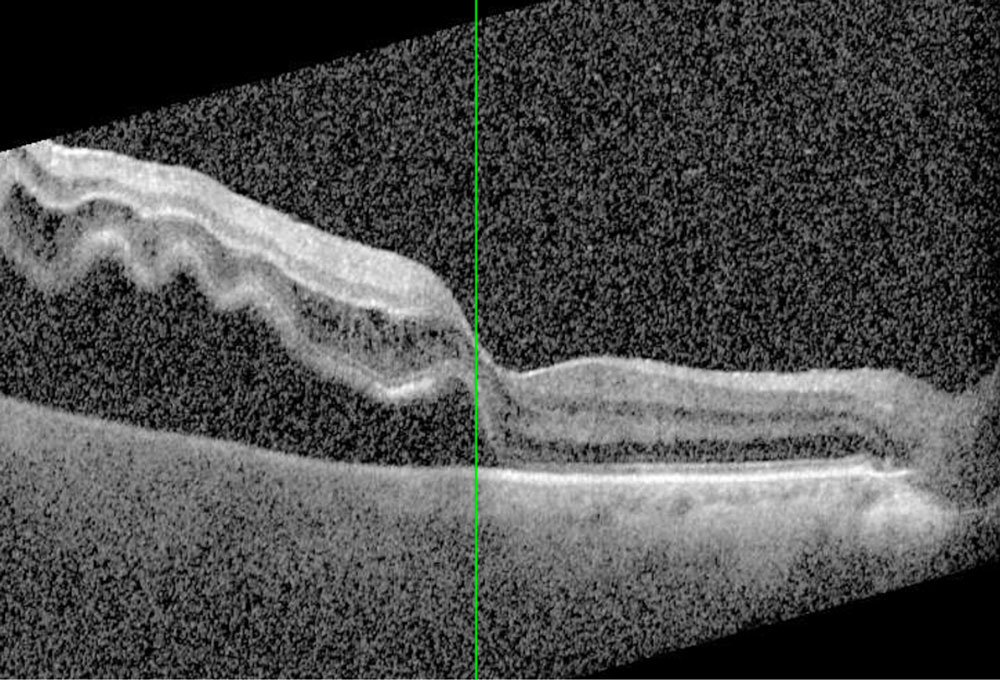

Un décollement de rétine survient lorsqu’elle se sépare de son support (l’épithélium pigmentaire rétinien).

Le diagnostic se fait lors d’un examen du fond d’œil.

L’ophtalmologiste visualise directement la zone décollée et recherche une déchirure ou une déhiscence rétinienne.